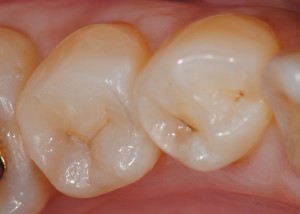

他の症例①